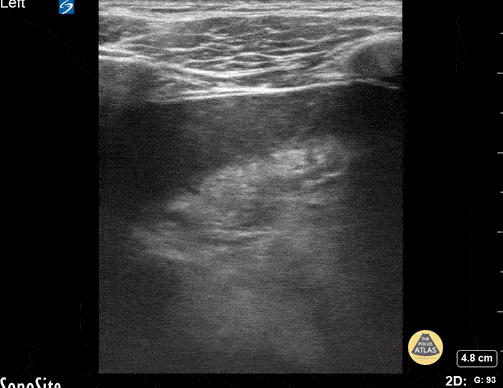

5 y/o with pneumonia- the image demonstrates hepatization of the lung consistent with pneumonia/consolidation. Contributor: Kathryn Pade, MD, Rady Children's Hospital San Diego